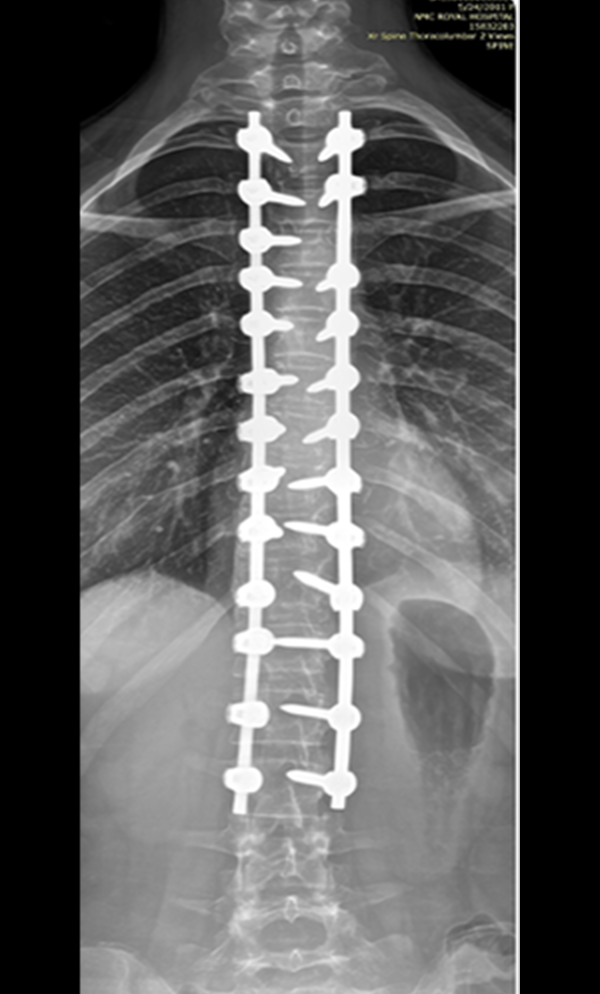

Gallery : Before - After